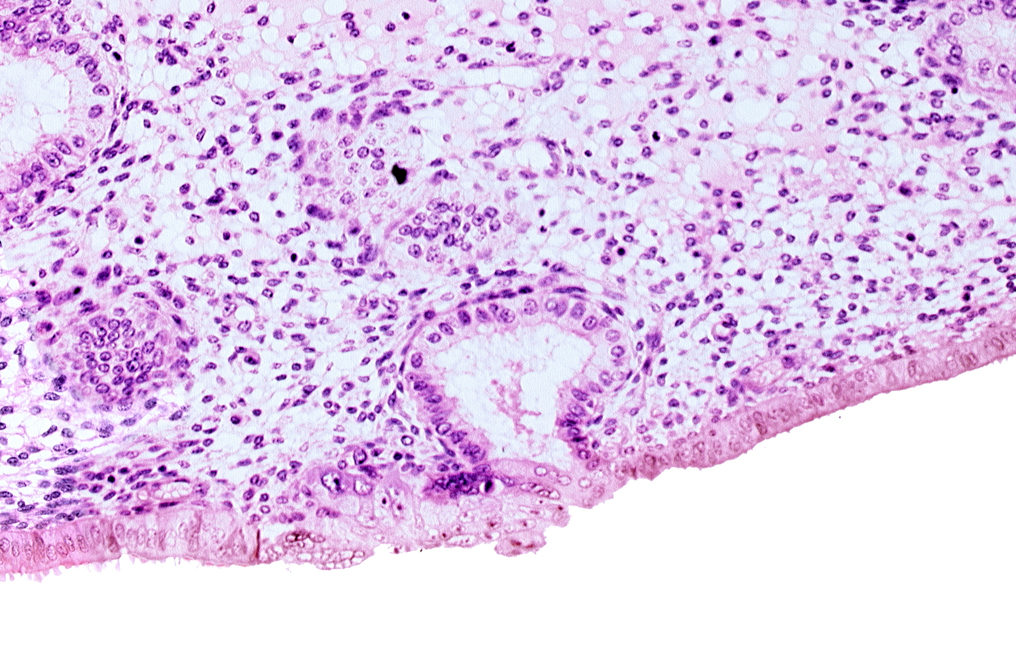

Carnegie Embryo #8020 | Location: 06-05-05

Keywords: edematous endometrial stroma (decidua), endometrial epithelium, lumen of endometrial gland, solid syncytiotrophoblast